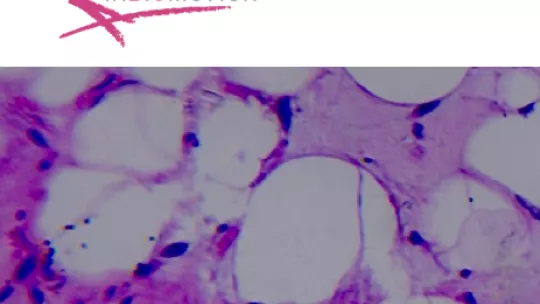

Inbiomotion develops diagnostic tests for predicting the risk that cancer patients may suffer bone metastasis. Bone metastasis occurs when a tumour growing in another part of the patient’s body spreads out through the bloodstream, overcomes all of the body’s defences, and colonises itself in the bone. These metastatic cancers are usually highly aggressive, painful, and ultimately result in the patient’s death.

The target market for Inbiomotion is patients with prostate or breast cancer, where bone is the most common site for metastasis. Some 75% of women with metastatic breast cancer and 90% of men with metastatic prostate cancer develop bone metastasis during the course of their disease. This will also happen with 15-30% of patients with other types of tumours, such as lung, colon, stomach, uterine, rectal, thyroid, or kidney.